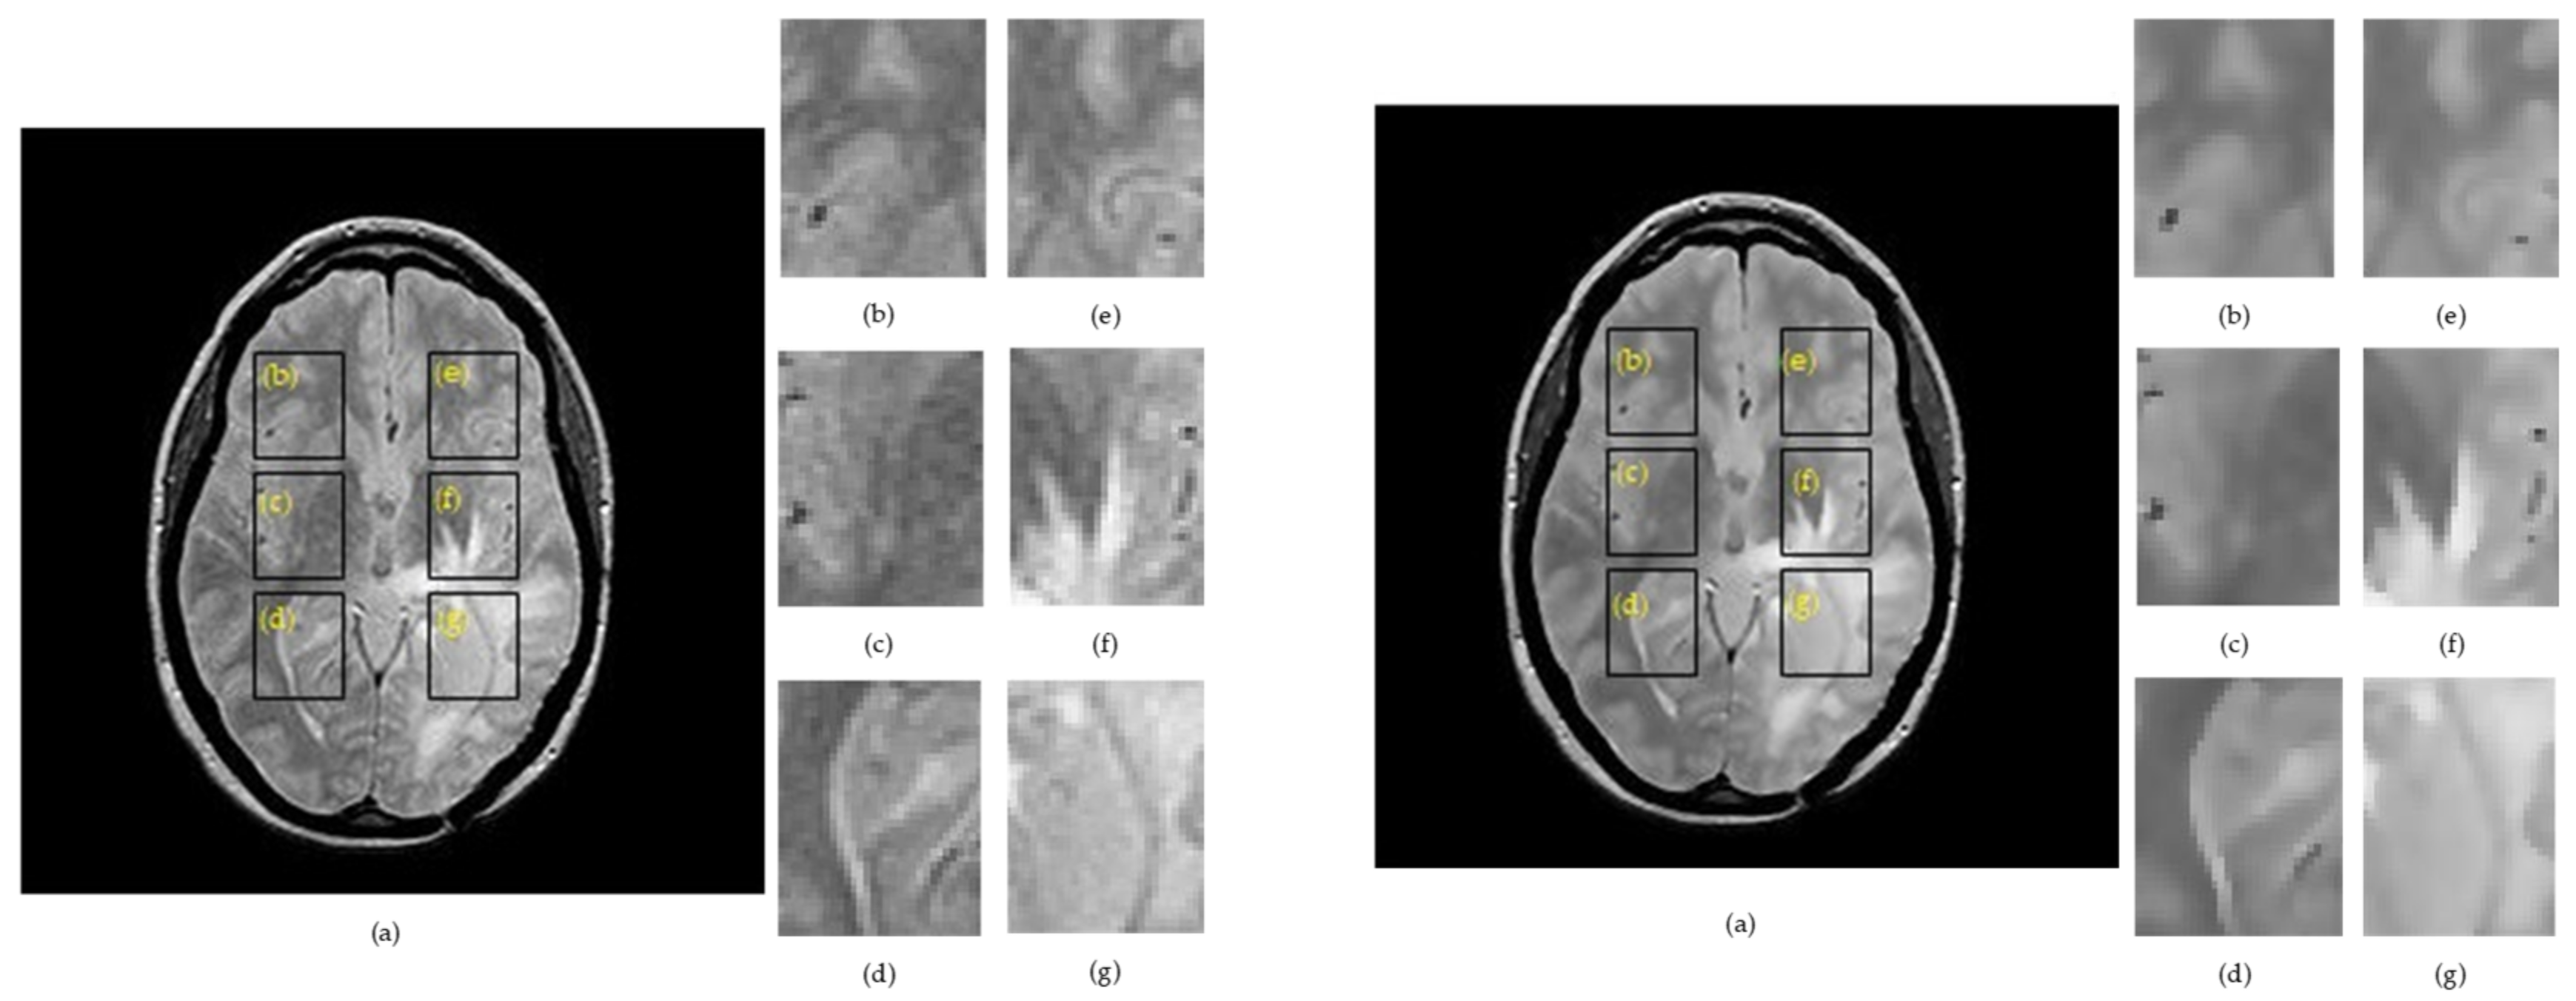

Figure 2 and Figure 3 show examples for the implementation of SSIMs and skeletonization for right– left correspondents for a raw image containing Rician noise (left panel) and a filtered image by the anisotropic diffusion filter (right panel).

The region of interests cut from the right hemisphere were labelled as ROI 1R, ROI 2R, ROI 3R, and their symmetry in the left hemisphere were denoted as ROI 1L, ROI 2L, ROI 3L. Figure 4 summarizes the skeletonization results for a patient with glioma by providing a direct comparison of the morphological skeleton transform between brain hemispheres. The skeletal maps for two correlated ROIs were overlapped to provide a facile evaluation of dissimilarities.